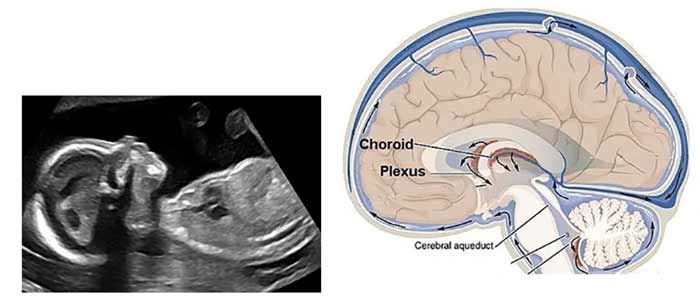

سونوگرافی آنومالی، لحظهای کلیدی در بارداری است که رشد جنین را با دقت بررسی میکند. گاهی در این اسکن، یافتهای مانند کیست در مغز جنین مشاهده میشود که ممکن است نگرانیهایی برای والدین ایجاد کند. این کیستها، که اغلب بهصورت لکههای کوچک در صفحه سونوگرافی ظاهر میشوند، میتوانند نشانهای گذرا یا علامتی نیازمند بررسی باشند.

سونوگرافی آنومالی، اسکنی دقیق در هفتههای 18 تا 22 بارداری است که ساختارهای جنین را ارزیابی میکند.

کیست کوروئید پلکسوس (CPC)، شایعترین کیست مغزی جنین، کیسهای مایعدار در بطنهای مغز است که مایع مغزی-نخاعی تولید میکند و اغلب بیضرر است.

مغز جنین از هفته ششم بارداری شکل میگیرد و تا هفته بیستم، ساختارهایی مانند بطنها و کوروئید پلکسوس تشکیل میشوند. کیستها، اغلب نتیجه تجمع طبیعی مایع در این نواحی هستند. بر اساس مطالعهای در Journal of Fetal Medicine (2024)، 1 تا 2 درصد جنینها کیست کوروئید پلکسوس دارند، اما تنها 5 درصد موارد با ناهنجاریهای کروموزومی مرتبط است.

کیست کوروئید پلکسوس (CPC)، شایعترین نوع کیست مغزی جنین، بهصورت کیسهای مایعدار (2 تا 10 میلیمتر) در بطنهای جانبی مغز ظاهر میشود. در سونوگرافی آنومالی، این کیستها به شکل نقاط تیره دیده میشوند و معمولاً دوطرفه هستند.

کیست آراکنوئید در فضای آراکنوئید، لایه محافظ اطراف مغز، تشکیل میشود و در سونوگرافی بهصورت کیسهای گرد و شفاف دیده میشود.

در سونوگرافی آنومالی، کیستها بهصورت نقاط سیاه یا کیسههای شفاف دیده میشوند. علائم در جنین معمولاً وجود ندارد، اما در صورت همراهی با هیدروسفالی، ممکن است رشد غیرطبیعی مشاهده شود. تشخیص دقیق با سونوگرافی 3D/4D یا MRI جنینی (پس از هفته 24) انجام میشود.